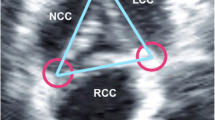

Piazza et al. [4] defined four parts of the aortic root: a virtual annulus formed by the joining basal attachments of the AV leaflets, the anatomic annulus formed by the ventriculoarterial junction, the sinotubular junction, and a crown-like ring formed by the insertion of the leaflets. Thus the structure of the aortic annulus as measured by echocardiographic means is the virtual ring or the hinge point of the AV cusps (Fig. 2).

a Three-dimensional model of the aortic root showing the location of the various annular rings and junctions. b The close relationship between these structures and the coronary ostia can be seen (reprinted with kind permission from Piazza et al. [4])

The mean AVA calculated by 2D-TTE was 0.69 ± 0.28 cm2 with peak and mean pressure gradients across the AV of 67.3 ± 34.5 and 39.9 ± 21.5 mmHg, respectively (Table 1). A high correlation was noted between the planimetry of AVA by 2D-TEE and RT3D-TEE (r = 0.81, P < 0.1); however, 2D-TEE planimetry showed a significantly larger AVA than RT3D-TEE (0.71 ± 0.26 cm2 vs. 0.61 ± 0.23 cm2, P < 0.05); Fig. 2). Figure 3 shows different imaging planes for the same AV, demonstrating the reason for the overestimation of AV size. Further, considering the RT3D-derived LVOTAp in the CE yielded a higher calculated AVA (0.8 ± 0.58 cm2) (Fig. 4).

a, b Linear correlation between the aortic valve (a) area and Bland-Altman analysis between RT3D-TEE and 2D-TEE (b). c A 2D-TEE image of a severely calcified aortic valve. d Live 3D-TEE reveals the original tricuspid valve with a funnel-shaped valvular opening. e Quantification of the exact valvular opening area. Red circles in b and c: The funnel-shaped valve results in overestimation of the aortic orifice area and underestimation of the aortic stenosis in 2D-TEE [14]

Overestimation of AVA by 2D-TEE. Before valve replacement is considered, the severity of stenosis must be accurately assessed. It is important to determine AVA using a flow-independent technique such as planimetry. In 2D methods, it is often difficult to capture the tip of the aortic valve leaflets at the moment of maximal systolic opening; this may lead to overestimation of AVA because of a “funnel” configuration. The example images show the imaging planes of a RT3D-TEE-acquired volumetric dataset with long-axis views (left) and en face views (right). Usual 2D planimetry at different levels could result in the different AVA dimensions of 1.15 cm2 and 0.75 cm2. This illustrates that optimal positioning of the imaging plane is essential for accurate planimetry of AVA